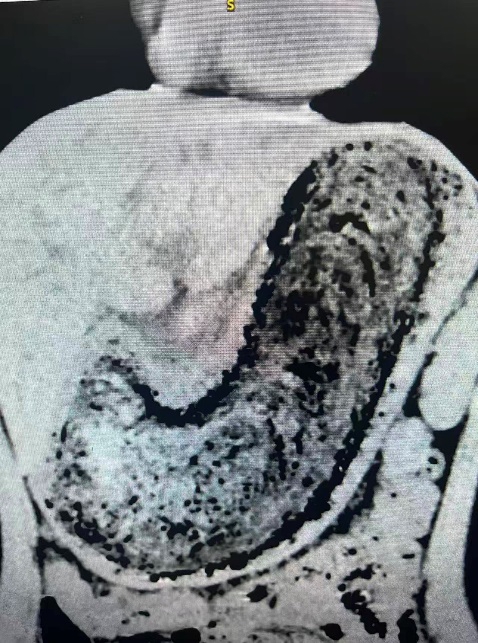

数月前,小田因反复腹胀、呕血和黑便,血红蛋白一度低至40g/L,情况危急。当地医院胃镜检查发现她患有“胃石症”。为寻求进一步治疗,今年6月,她来到孟祥军主任医师专家门诊。进一步的CT和胃镜结果显示,其胃腔内竟然塞满了一个约30cm×20cm的致密毛发团,不仅堵塞了整个胃室,还导致胃黏膜出现多处深大溃疡。

患者入院上腹CT结果